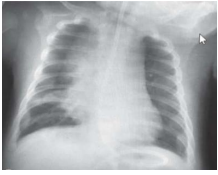

Uma criança de 18 meses de idade com história de chiado recorrente é levada ao pronto-socorro com queixas de tosse persistente, febre de baixo grau e dificuldade respiratória. A mãe relata que os sintomas pioraram nas últimas 24 horas. Na radiografia realizada (conforme imagem), a criança apresenta tiragem subcostal, sibilos difusos na ausculta pulmonar e saturação de oxigênio de 91%.

No que diz respeito ao quadro clínico e aos achados radiológicos, assinale a alternativa que apresenta o diagnóstico e o manejo adequados.